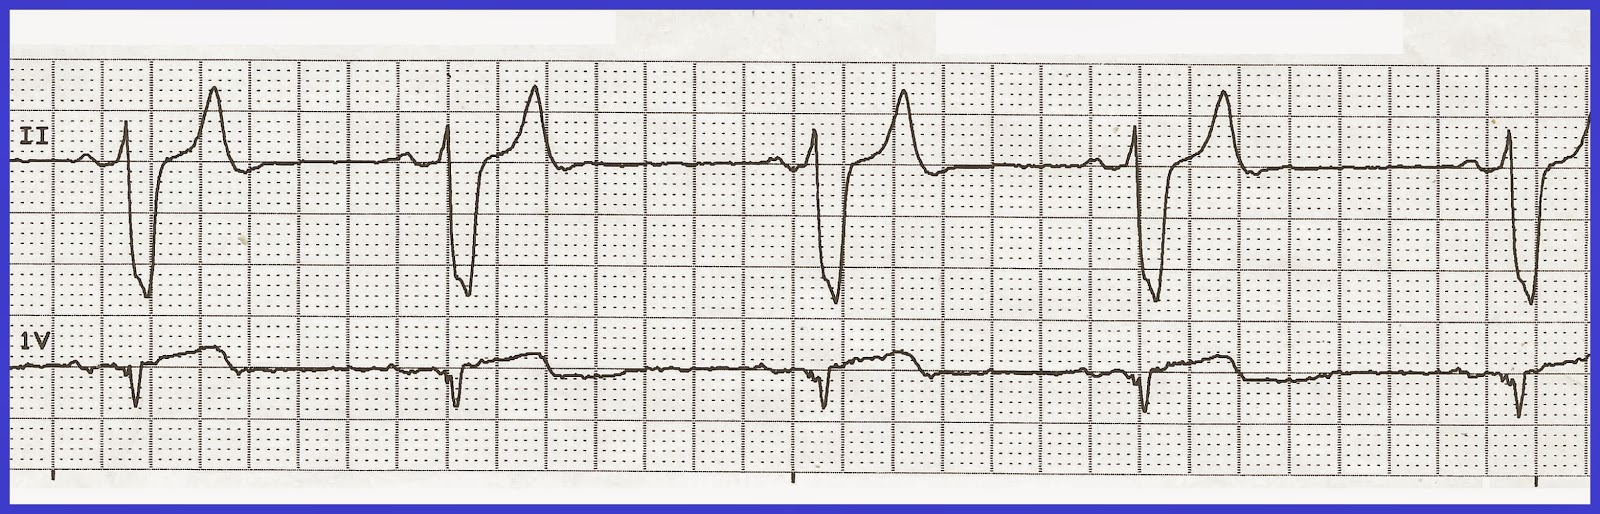

Брадикардия как поднять пульс